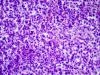

опухоль |

Не могли ли Вы увеличить фото для пересмотра стеклопрепаратов.. т.к.наблюдается в ядрах признаков соли и перца без атипических митозов.

Не исключается забрюшинная нэйроэндокринная опухоль с метастазами в почку и печень. |

2 фото рака почки из атласов. Мне представляется,что опухоль,особенно на втором фото,похожа на консультируемую. Эскизы прикрепленных изображений

Синеклеточность, скудность цитоплазмы, большее ядерно цитоплазматическое соотношение, массивность инфльтрации в печени, почке и забрюшинной клетчатки, без патологических митозов, метастазы в трех локализации указывает за ПНЭО злокачественной.